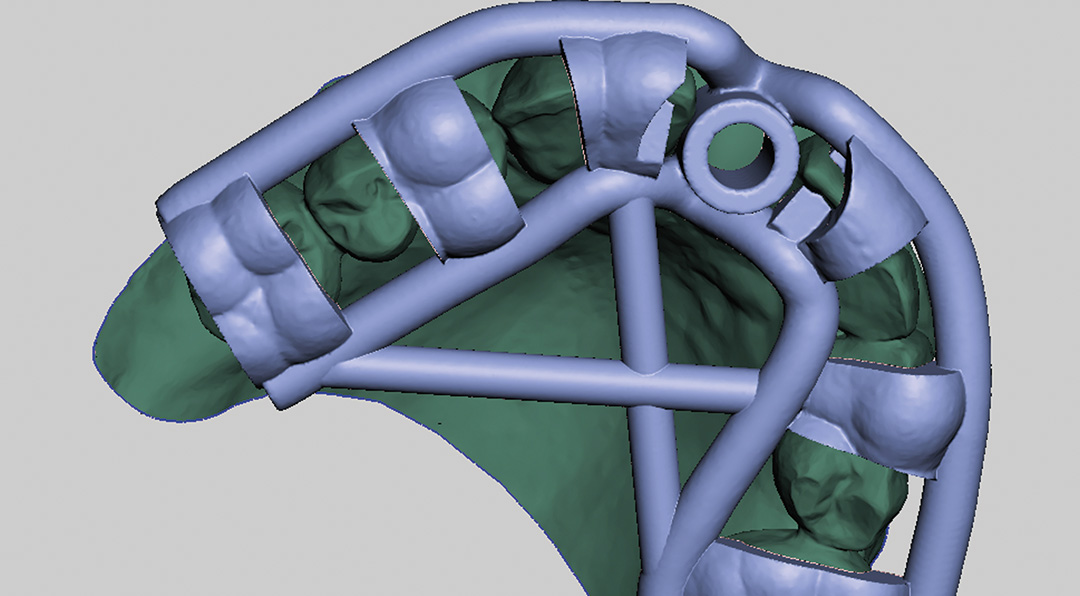

A CBCT and intraoral scans assessed the site, and coDiagnostiX® software was used to plan implant positioning and design the surgical guide virtually. The plan included immediate implant placement, filling the buccal gap with a xenograft and a soft tissue graft from the maxillary tuberosity to enhance soft tissue thickness in this high-risk aesthetic area.

An intraoral scan and a CBCT image were acquired as part of the comprehensive assessment. The images were matched using dental Blue Sky Bio software to facilitate the design of the surgical guide, using a prosthetically-driven planning approach to find the ideal 3D position of the implant. The surgical template was 3D printed and sterilised in preparation for surgery.